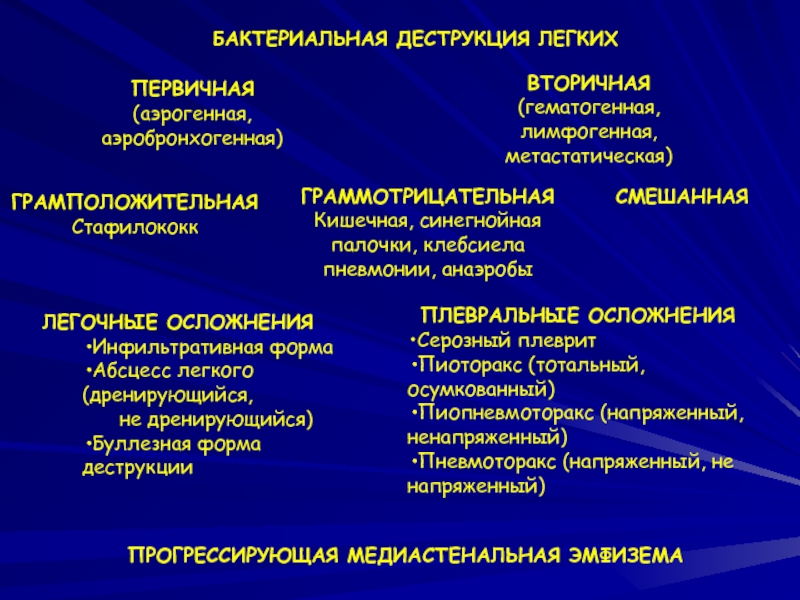

Бактериальная деструкция легких у детей презентация - 88 фото